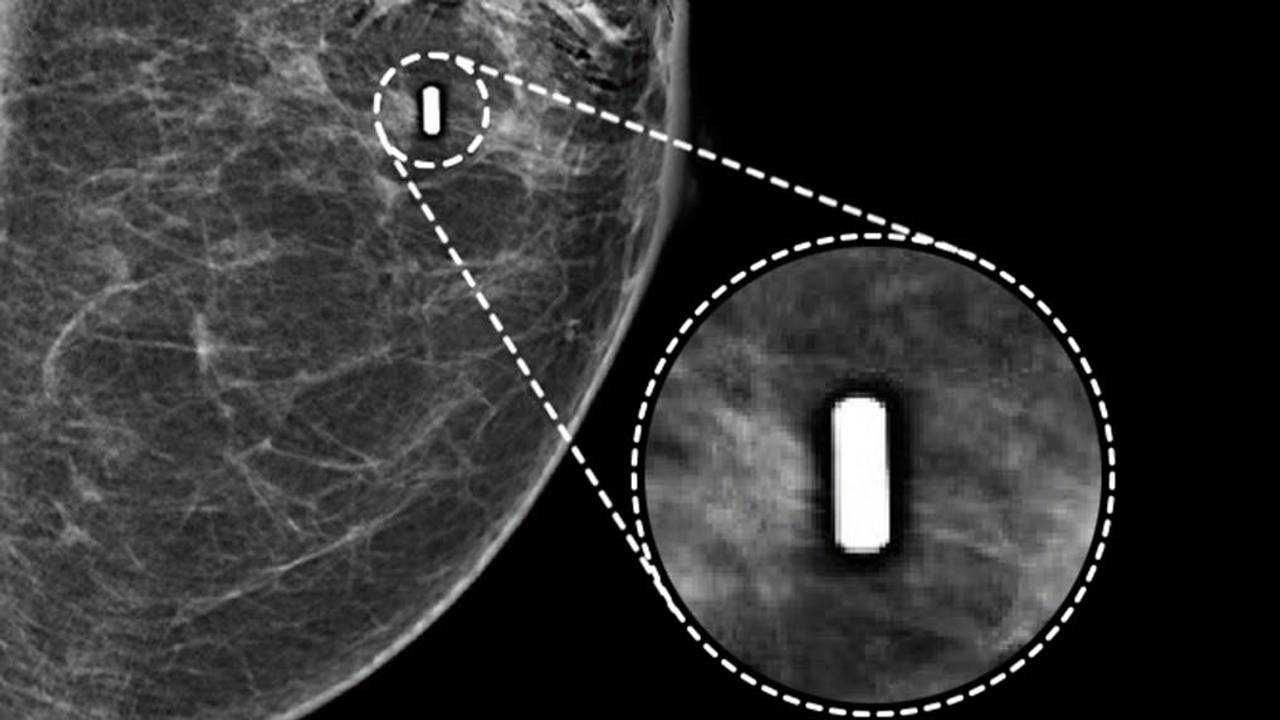

Met de nieuwe uitvinding, de zogenaamde Pintution, gaat dat anders. De tumor wordt gemarkeerd met een magneetje, zo groot als een rijstkorrel. Deze wordt met een spuit ingebracht. De chirurg kan met een sensor tot op de millimeter nauwkeurig zien waar de tumor zich bevindt.